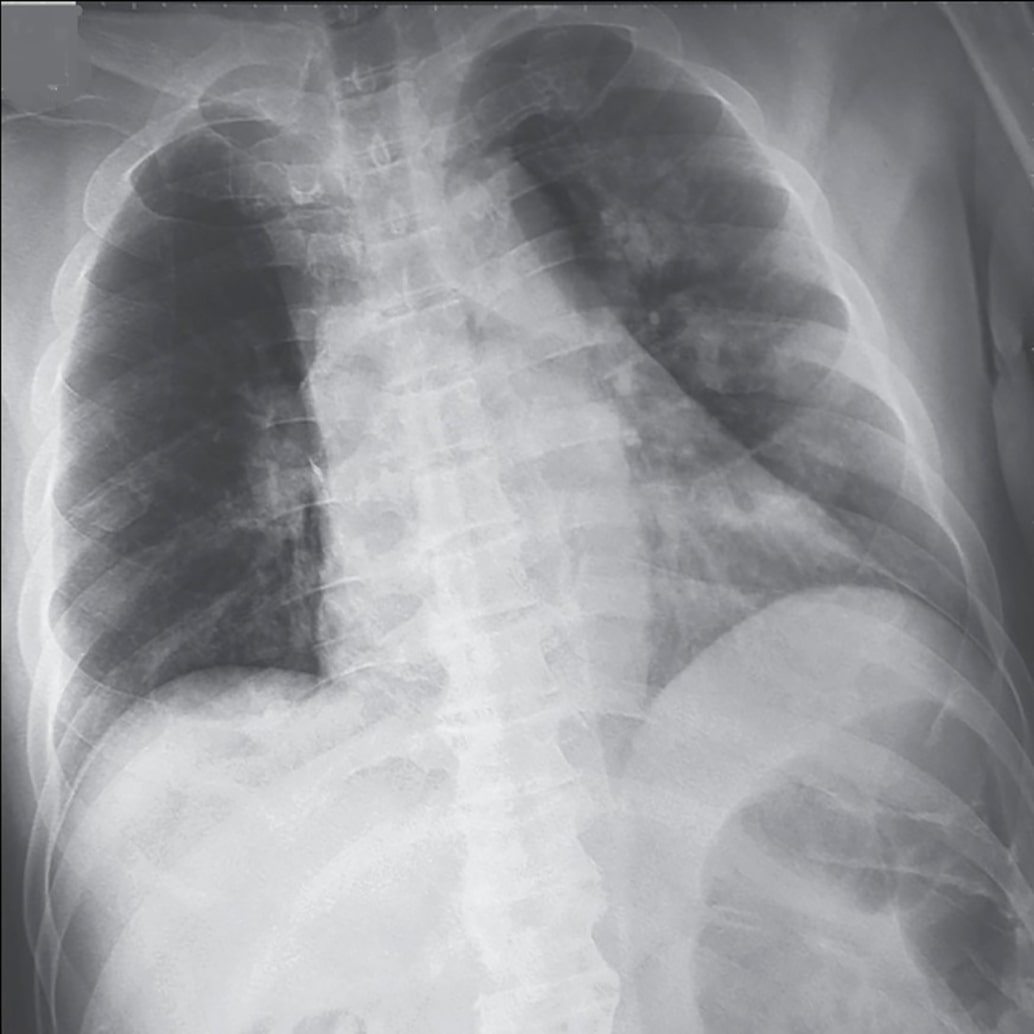

Appendix B More Grad-CAMs of the COVID-CXNet Model with Lung Segmentation Preprocessing

Refer to caption

Figure 21: Grad-CAMs from COVID-CXNet with lung segmentation module